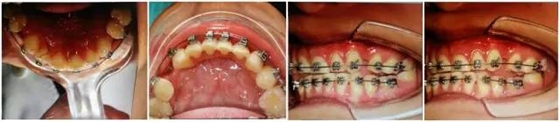

每一位臨床醫(yī)生每天都會面臨各種困惑和難題,只要我們堅持思考,善于溝通、勤于實踐,(牙合)學的神秘大門將會為我們敞開。這是權老師最初在(牙合)學群里分享的一句話。最近,權老師在(牙合)學群里分享自己的病例,“堅持思考,善于溝通、勤于實踐”,她不僅用這樣的話激勵群里的每一位同仁,更一直在行動著。讀讀病例,讓我們開始思考…… 病例:患者,女,22歲。 主訴:8年前曾行正畸矯正,現(xiàn)因美觀及功能需求,要求重新矯治。 現(xiàn)病史:2個月前,開始戴用矯治器,以0.012Niti初始絲,近2個月來無明顯不適。2天前,上前牙開始出現(xiàn)咬硬物疼痛,冷熱刺激痛,自覺松動。 檢查:上前牙松(Ⅱ)°,牙齦紅腫,牙周膜間隙增寬。(如照片所示)

以上群里多位醫(yī)生的探討基本與權老師的處理方案接近。權老師的最終治療是通過樹脂暫時恢復尖牙引導功能,側方引導,使上下前牙分離了,緩解前牙創(chuàng)傷;做完舌側的功能恢復,后牙打開較多,在某種程度上對后牙也有很大保護。

(以下為治療后的照片:患者癥狀得到了良好改善。)

足以看出,尖牙保護(牙合)在臨床工作中的重要作用,它是以尖牙為支撐,對其他牙齒起到保護作用。其特點是正中關系(牙合)與正中(牙合)協(xié)調(diào);側方咬合運動時,工作側只有尖牙保持接觸非工作側牙齒不接觸;在作前伸咬合運動時,上下頜前牙切緣相對接觸,后牙不接觸。尖牙具有適合制導的舌面形態(tài),可使用(牙合)力趨于軸向;牙根長且粗大,支持力強;尖牙位居牙弓前部,在咀嚼時構成第Ⅲ類杠桿,能抵御較大的咀嚼力;以及尖牙牙周膜感受器豐富,對刺激敏感,能及時調(diào)整反應都是尖牙的有利條件。尖牙形態(tài)的恢復在此例正畸治療中,對前牙、后牙都起到了很好的保護作用,也能保證后期按照標準(牙合)進行(牙合)重建時后牙無干擾。功能在先,美觀在后,權老師為您展示了這樣的治療理念。